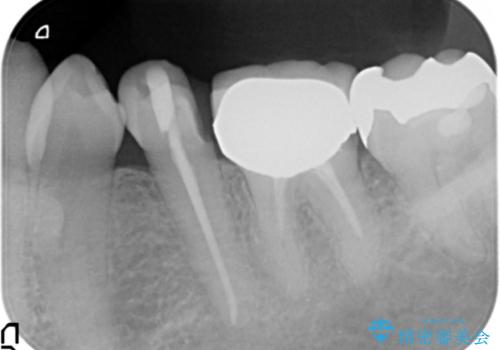

- 違和感や疼きのある左側小臼歯に加え全体的にクラウンや詰め物のやりかえを希望され来院されました。

治療後に再発した虫歯や根管再治療に加え、穴の空き症状のある上顎左側小臼歯は抜去を行いインプラントによる機能回復治療を計画します。

X線写真検査ではわからない虫歯も外してみると再発していることがあります。虫歯を丁寧に取り除き、再発を防ぐべく精密なクラウンの作製を行うことが長期的な予後につながります。